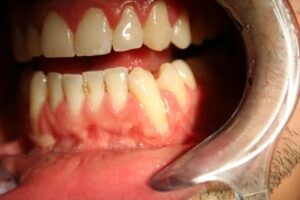

Receding gums are best avoided for several good reasons. Gum recession can lead to tooth sensitivity and even affect your smile, but that’s not all. Your gums (or gingiva) are critical in protecting the bone that holds your teeth in place. If the gums begin to shrink away, tooth roots can be exposed. Tooth roots can be more easily worn away than enamel covered surfaces and are susceptible to decay.

Exposed tooth roots that cause sensitivity

Shrunken gums

Poor oral health: When bacteria in plaque (biofilm) builds between the gums and teeth, the gums surrounding the teeth can become inflamed. This inflammation, if left untreated, can result in deterioration of the gums and supporting bone structure. This then leads to gum recession and periodontal disease, a severe gum infection.